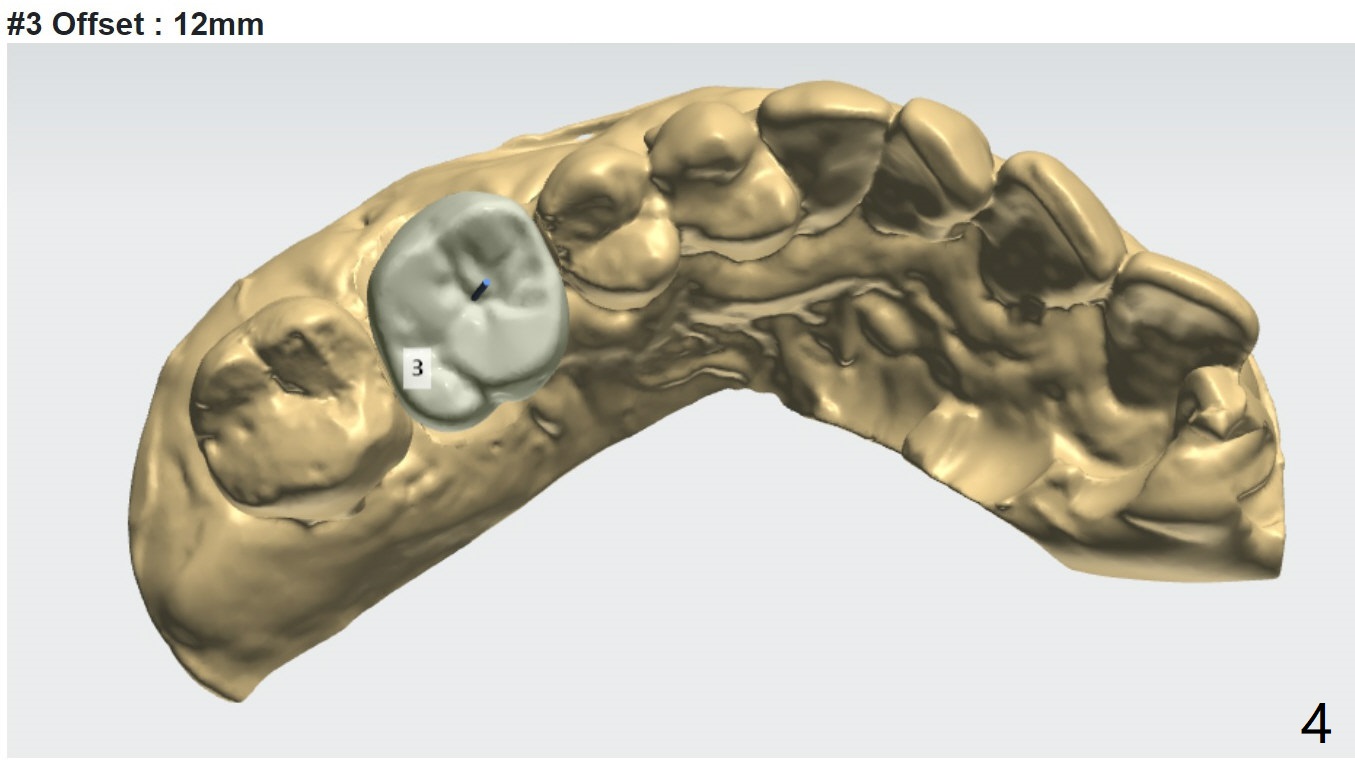

Implant Placement Level and Angulation to Sinus Floor

Return to No Deviation Torque 劈开术